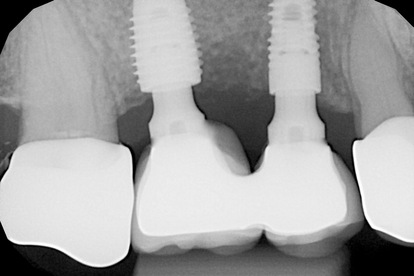

E’ stato eseguito l’inserimento di 2 impianti Advan GTB in posizione 15 e 25 in osso non rigenerato. Contestualmente è stato eseguito un intervento di rialzo di seno bilaterale con osteotomi ed inserimento di Bone Graft particolato di origine Bovina, ottenendo un “Grande” rialzo del pavimento del seno mascellare ma con accesso “crestale”, e sono poi stati inseriti 3 impianti Advan GTB SINUS LIFT in posizione 16, 26, 27. Tutti gli impianti sono stati fatti guarire sommersi. Dopo 6 mesi, ottenuta la rigenerazione intra-sinusale peri-implantare, si è proceduto alla scopertura ed al carico protesico.